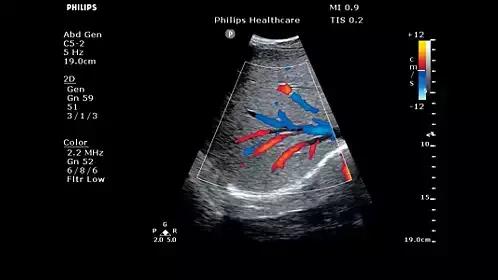

高分辨率血流:FloVue

FloVue 利用飞利浦在多普勒信号处理技术和能量成像技术领域的丰富经验,提供了一个全新的血流成像模式。它不依靠取样角度的偏转,也不依赖探测速度标尺的调整,可以明显提升对微细血管的血流探测能力,并且对大血管管壁成像及管壁斑块的诊断有着较大的帮助。